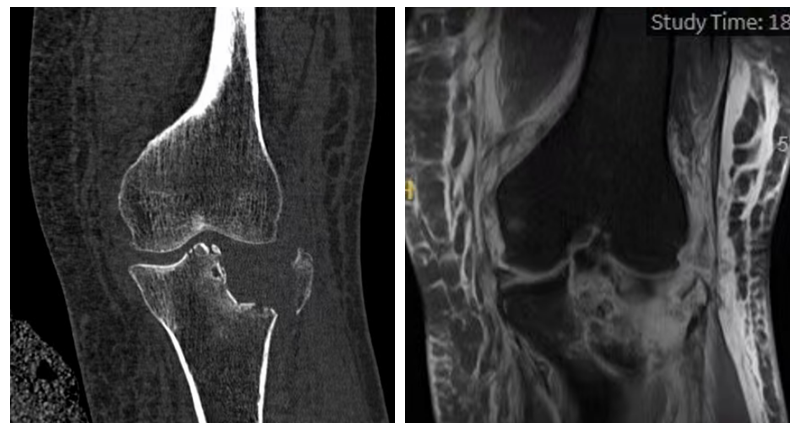

胫骨平台骨折的陷阱在于:X光片看到的只是冰山一角。要想术后不“踩雷”,术前必须拥有透视眼。

三维CT重建:清晰还原了李奶奶外侧平台严重的塌陷地图,精确计算了骨缺损的深度和范围,为制定“植骨+撬拨”术前规划提供依据。

核磁共振(MRI):揭开了软组织损伤的面纱——明确了内侧副韧带(MCL)和外侧半月板的损伤程度。

三维CT重建图及MRI影像可见外侧平台严重塌陷,内侧副韧带及外侧半月板损伤。